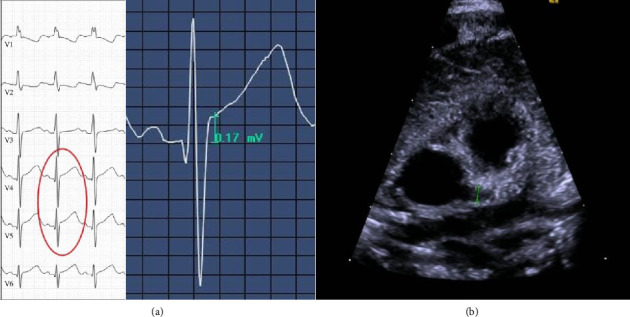

背景与目的:肠病毒(EV)主要引起轻度感染,但已发现对新生儿的影响更为严重。本研究的目的是描述5例出现EV感染中枢神经系统(CNS)的新生儿的症状、实验室检查、治疗、住院时间、影像学和结局。病例研究:所有患者在首次就诊时均有败血症和/或中枢神经系统感染的迹象,并使用脑脊液(CSF)逆转录酶聚合酶链反应(RT-PCR)进行诊断。1例出现癫痫发作和冠状动脉扩张,经左乙拉西坦、静脉注射免疫球蛋白、强的松龙和乙酰水杨酸治疗后恢复。该患者也是唯一一例脑脊液异常,包括单核细胞增多症。3/5患者血c反应蛋白轻度升高,而白细胞介素-6在发病时正常,随后升高(58.7 ~ 310 mg/dL)。5/5组中性粒细胞/淋巴细胞比值升高(1.02 ~ 4.83)。抗生素治疗4 ~ 7 d;住院时间7 ~ 13天。2/5脑超声检查,两项均正常。发生癫痫发作的患者进行了脑磁共振成像,未发现病理结果。5例患者的临床结果均良好。结论:新生儿出现脓毒症但无明显病灶,应考虑EV CNS感染,可通过CSF PCR检测诊断。诊断导致早期停止抗生素治疗和缩短住院时间。患有EV感染的新生儿应筛查心脏并发症,严重者应接受IVIG治疗。脑脊液异常可能预示更严重的病程,需要更密切的监测。

Background and Objectives: Enteroviruses (EV) mainly cause mild infections but have been found to affect neonates more severely. The aim of this study is the description of symptoms, laboratory findings, treatment, duration of hospital stay, imaging, and outcome in five neonates presenting with EV infection of the central nervous system (CNS). Case Study: All patients had signs of sepsis and/or CNS infection at first presentation and were diagnosed using cerebrospinal fluid (CSF) reverse transcriptase polymerase chain reaction (RT-PCR). One developed seizures and dilated coronary arteries and recovered after treatment with levetiracetam, intravenous immunoglobulins (IVIGs), prednisolone, and acetylsalicylic acid. This patient was also the only one to show CSF abnormalities including mononuclear pleocytosis. C-reactive protein in blood was slightly elevated in 3/5, while interleukin-6 was normal at onset and later increased (58.7-310 mg/dL) in all patients. Neutrophil-to-lymphocyte ratio was elevated (1.02-4.83) in 5/5. Antibiotics were given for 4-7 days; hospital stay lasted 7-13 days. Cerebral ultrasound was done in 2/5 and was normal in both. The patient who developed seizures underwent brain magnetic resonance imaging without pathological findings. The clinical outcome was favorable in all of our five patients. Conclusions: In neonates who appear septic without an apparent focus, EV CNS infection should be considered and can be diagnosed by CSF PCR testing. Diagnosis leads to earlier discontinuation of antibiotic treatment and shorter hospital stay. Neonates with EV infection should be screened for cardiac complications and in severe cases treated with IVIG. CSF abnormalities might predict a more severe disease course and justify closer monitoring.